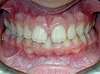

Cas n°4

Incisives en position inversée et malposition antérieures.

Durée du traitement: 2 ans, traitement commencé à 11 ans